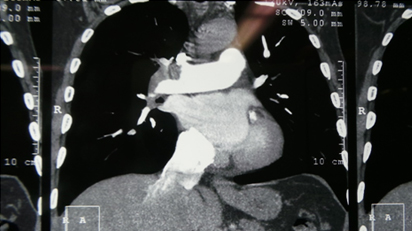

CT Pulmonary Angiography Showing Intra Pulmonary Filling defects

Filling Defects Within Pulmonary Artery